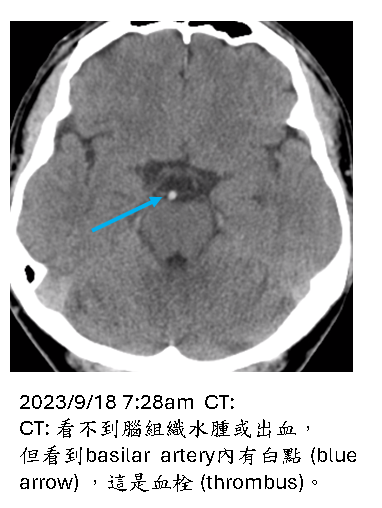

所以最終basilar artery 為何會血栓形成還是不明。請詳細觀看以下病例影像描述:

憂鬱症患者,被發現躺在地上,意識混亂,

最近兩週有發燒、頭痛、咳嗽症狀。

檢驗CPK、lactate升高,metabolic acidosis, 起初被認為是meningitis, serotonin syndrome。